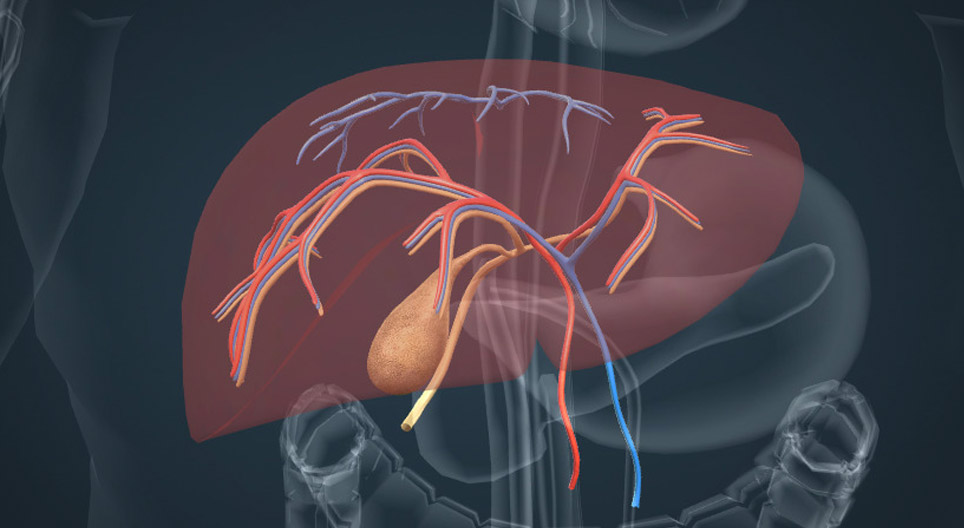

The anatomy and functions of the liver

The anatomy and functions of the liver

The liver is a vital organ that plays an important role in the digestion of fats, detoxification and metabolism.